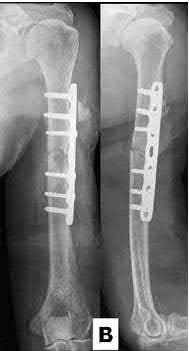

A 51-year-old carpenter presents with a distal humerus nonunion (Figures A and B). After repair of the nonunion, he is lost to follow up for 3 months and then presents to your clinic pain-free and with evidence of fracture union. On examination the elbow arc of motion is 10-80 degrees. Following a brief failed trial of conservative management, you recommend:

Limited flexion outside a functional range of motion (30-130 degrees) can be quite debilitating, and it is often addressed with open release of the posterior bundle of the MCL and posterior capsule and excision of osteophytes.

A frequent complication of distal humerus fractures is post-traumatic stiffness. This patient has had multiple procedures about the distal humerus, and the question stem implies that he did not complete a structured range of motion protocol following the repair of his nonunion. Beyond a trial of conservative management, there are many techniques described for capsule and soft tissue releases as well as bony resections if heterotopic ossification is present. This patient's severely limited flexion would best be addressed with a release of the posterior bundle of the MCL, and with flexion